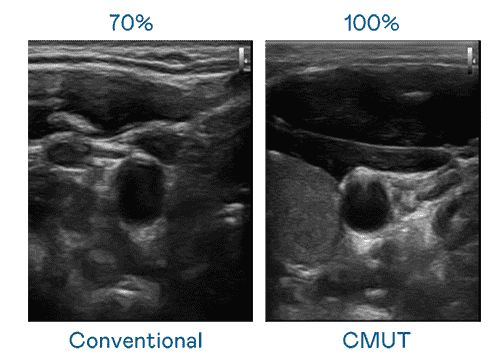

CMUT 技术是一种用电容式微机电元件来产生超音波讯号的技术。。与传统 PZT 压电式技术相比,,,,CMUT 频宽增加 30%,,,,更宽频的超音波讯号让影像解析度大幅提升,,,,是实现高影像品质医疗超音波扫描、、、促进精准医疗发展的关键技术。。。

大频宽带来超清晰影像

超音波影像的解析度高低,,,首先取决于探头能发出的讯号频宽。。。。PG国际 CMUT 可提供高清晰的超音波讯号,,,提供高频宽、、、、高灵敏度、、、影像纹理细节更高的超音波影像,,协助医护人员缩短影像判读时间及利用精准的医疗影像进行诊断。。